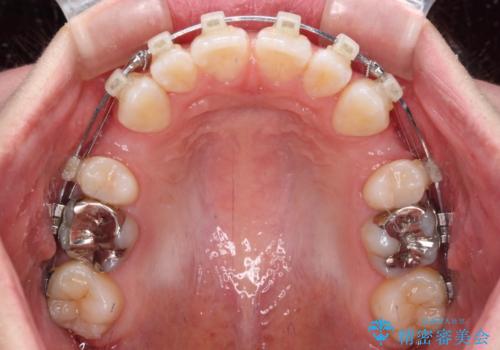

- クリアブラケット

- 1年6ヶ月

- 前歯の出っ歯と口元の閉じにくさを気にして来院された患者様です。

口元を積極的に引っ込めるために、上下左右の小臼歯4本を抜歯することとしました。

4本の歯を抜歯したことで、飛び出していた口元が引っ込み、横顔が大きく改善されました。